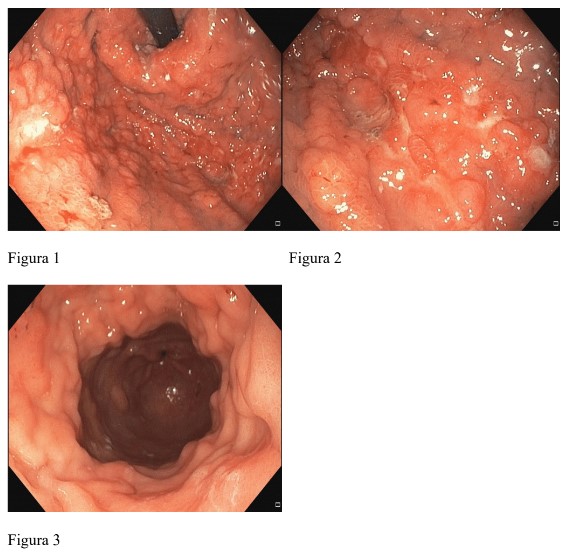

Homem de 60 anos, com dispepsia, disfagia e pirose, submetido a endoscopia digestiva alta que revelou aspecto infiltrativo difuso, nodular e friável de toda a mucosa gástrica (desde o cárdia ao piloro), com múltiplas úlceras aleatórias de fundo nacarado (Figura 1 e 2) e deficiente distensibilidade das paredes com a insuflação(Figura 3). Os aspectos endoscópicos eram sugestivos de linite plástica. As biopsias revelaram carcinoma de células pouco coesas em anel de sinete (estadiamentoT3N3M1).